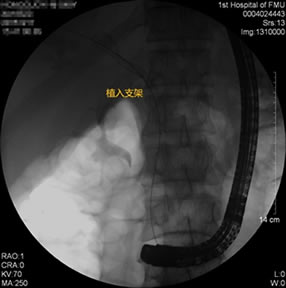

胃毕-Ⅱ术后乳头倒置 胃毕-Ⅱ术后胰管胆管双支架植入 胃毕-Ⅱ术后金属支架植入

胃毕-Ⅱ术后肝门部胆管狭窄 胃毕-Ⅱ术后金属支架植入